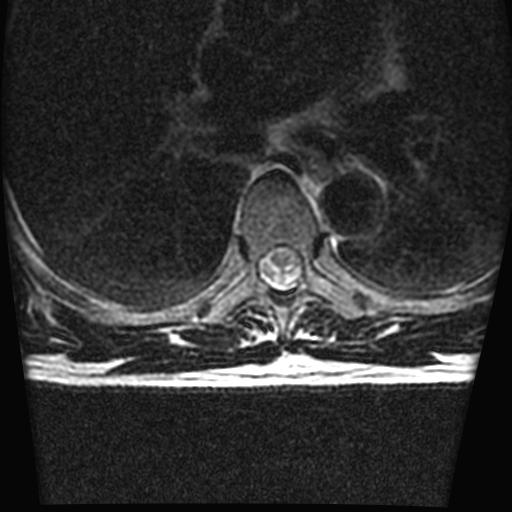

标题: MRI0985:胸椎.68岁男性,胸部疼痛,

68岁男性,胸部疼痛,不适。

胸7椎体楔状变形及信号异常,附件未见明显异常信号.椎间隙正常.未见软组织块影.考虑骨质疏松所致压缩性骨折可能大.

胸7椎体楔状变形及信号异常[t1t2 均为低信号],附件未见明显异常信号.椎间隙正常.未见软组织块影.考虑陈旧性压缩性骨折伴退变。

首先需除外单发成骨性转移瘤可能。